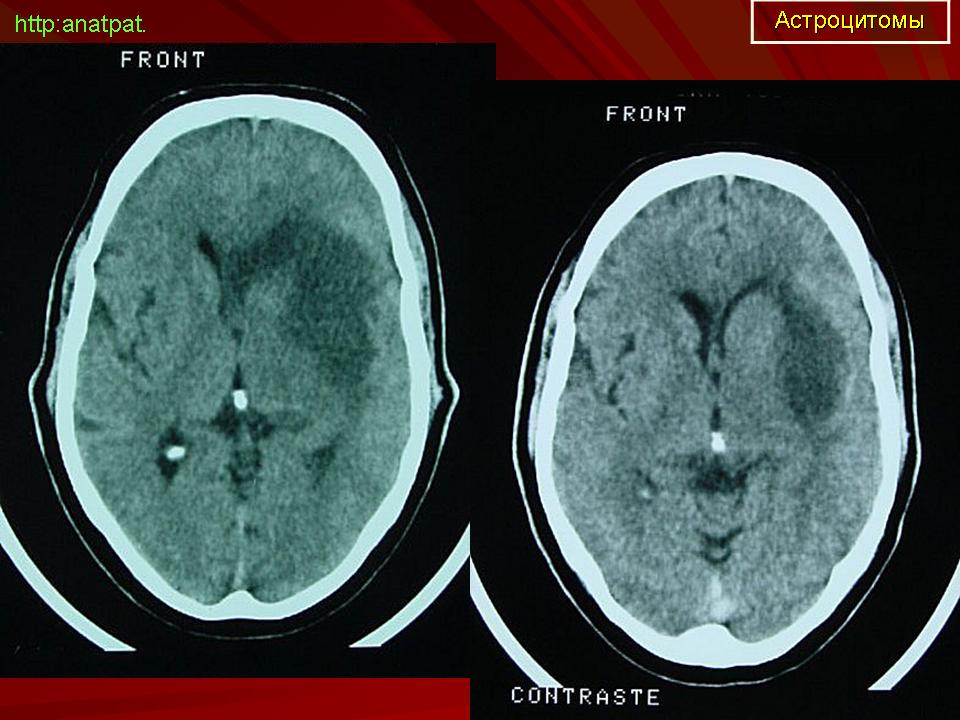

ГМ. Астроцитома. +

Астроцитома.